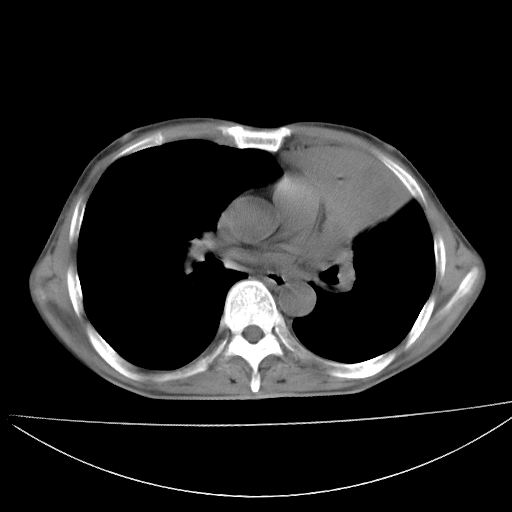

以下是引用杀毒软件在2009-4-28 17:58:00的发言:[br]考虑----左肺慢性肺脓肿形成继发上叶含气不良---抗炎后复查---待排肿瘤所致[br][br][本贴已被 杀毒软件 于 2009-4-28 18:01:26 修改过]